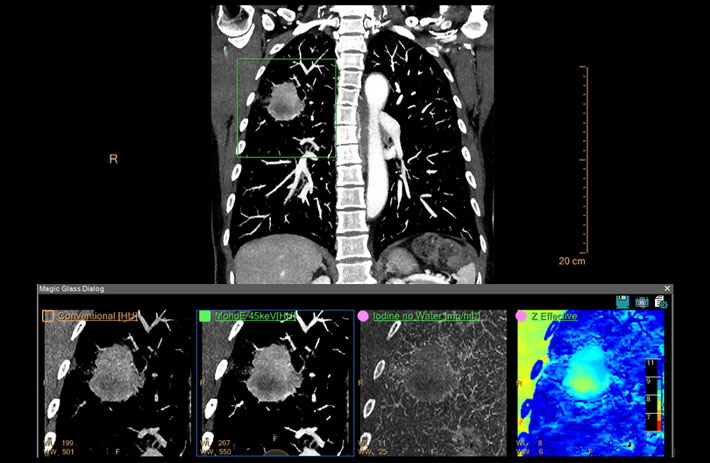

Mit dem Spektral-Detektor-CT werden Spektraldaten automatisch bei jedem Scan erfasst. Die Informationen stehen jederzeit auf der Scankonsole, der CT-Workstation sowie an jedem PACS-Arbeitsplatz zur Verfügung, sodass es nicht notwendig ist, den Patienten erneut zu scannen, bspw. wenn initial zufällige Anomalien festgestellt wurden. Dadurch profitieren Anwender durch eine höhere Diagnosesicherheit und weniger Nachuntersuchungen auf anderen bildgebenden Systemen. Unsere Fallsammlung zeigt, welchen klinischen Mehrwert der Spektral-Detektor-CT in unterschiedlichsten Anwendungsbereichen in der klinischen Routine bringt. Jede Woche gehen neue Fälle live.